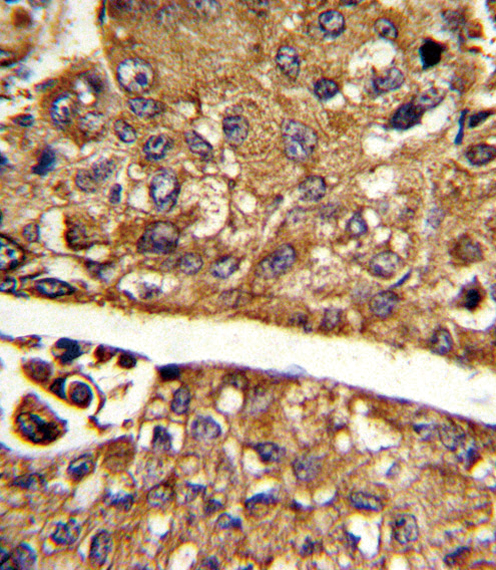

- Formalin-fixed and paraffin-embedded human hepatocarcinoma reacted with MDH1 Antibody (C-term), which was peroxidase-conjugated to the secondary antibody, followed by DAB staining. This data demonstrates the use of this antibody for immunohistochemistry; clinical relevance has not been evaluated.